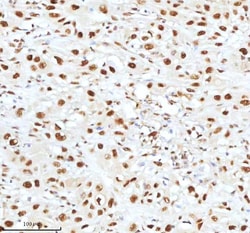

Reconstitute with 0.2 mL of distilled water to yield a concentration of 500 μg/mL. Positive Control - WB: human LNCAP whole cell, human Hela whole cell, human 293T whole cell, human HepG2 whole cell, human Jurkat whole cell, human K562 whole cell, human A549 whole cell, human A431 whole cell. IHC: human bladder cancer tissue, human bladder cancer tissue, human colon adenocarcinoma tissue, human colon adenocarcinoma tissue, human glioblastoma tissue, human glioblastoma tissue, human liver cancer tissue, human liver cancer tissue, human lung adenocarcinoma tissue, human lung adenocarcinoma tissue, human pancreas ductal adenocarcinoma tissue, human pancreas ductal adenocarcinoma tissue, human testicular seminoma tissue, human testicular seminoma tissue. ICC/IF: U2OS cell. Flow: A431 cell. Store at -20°C for one year from date of receipt. After reconstitution, at 4°C for one month. It can also be aliquotted and stored frozen at -20°C for six months. Avoid repeated freeze-thaw cycles.

| Flow Cytometry, Immunohistochemistry (Paraffin), Western Blot, Immunocytochemistry | |